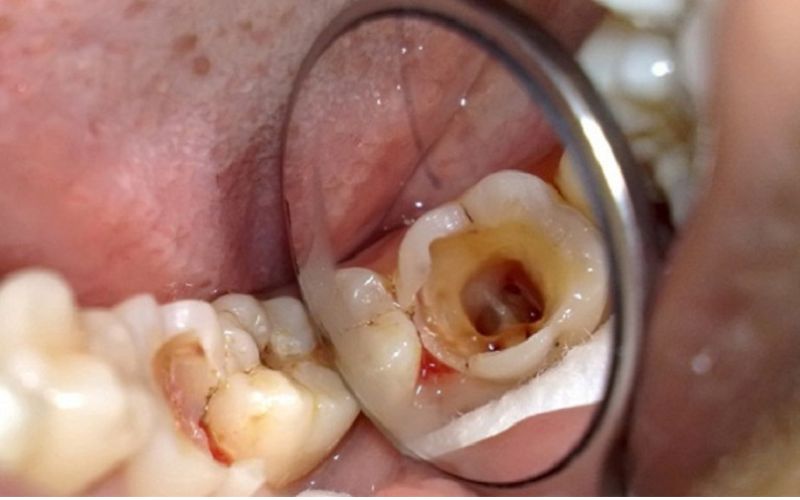

Giai đoạn đầu, vi khuẩn sâu răng chỉ tấn công các mô cứng bên ngoài. Sau đó, sâu nặng hơn sẽ bắt đầu phá hủy đến tủy răng và các phần khác. Lúc này, bệnh nhân dễ bị viêm tủy cấp tính, lâu dần thành mãn tính, cuối cùng là hoại tử tủy. Cùng với đó, dịch trong tủy sẽ tràn ra và dẫn đến nhiều biến chứng:

- Mất màu sắc và hình dạng: Răng sâu dễ chuyển sang màu nâu hoặc đen, làm mất đi vẻ đẹp tự nhiên của nụ cười.

- Biến dạng cấu trúc: Mô răng bị phá hủy dẫn đến hình dáng răng bị biến dạng.